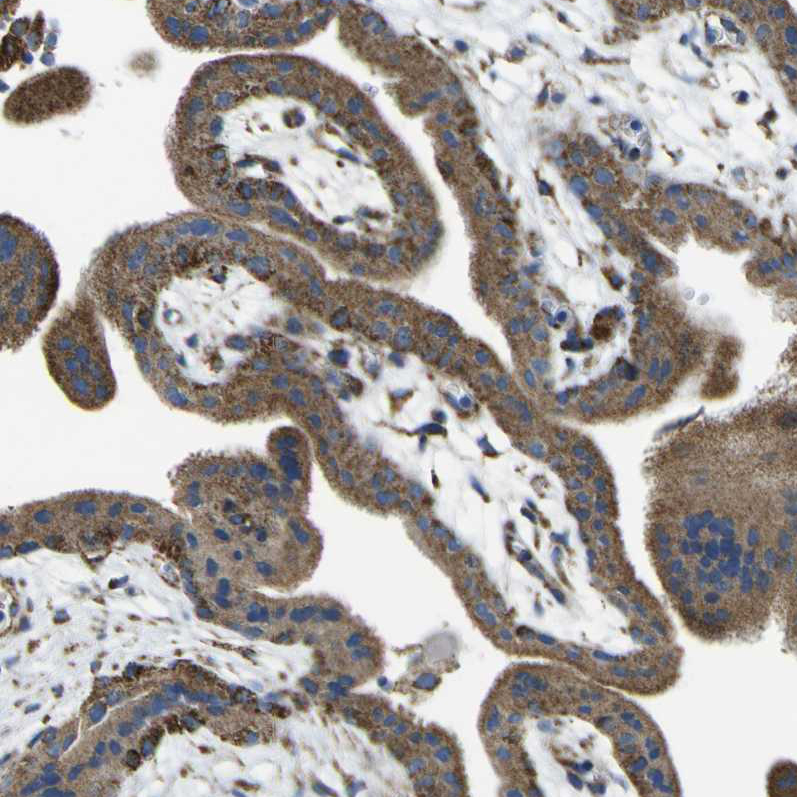

Immunohistochemical staining of human gastrointestinal shows strong granular cytoplasmic positivity in glandular cells.